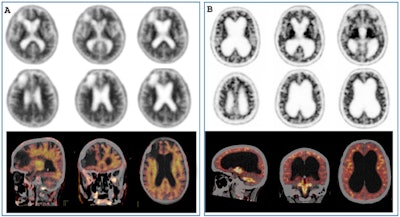

Pitfalls and artifacts in amyloid PET imaging. (A) F-18 florbetapir PET/CT scan of a patient with right frontal stroke and brain atrophy. The PET/CT fusion images clearly show no difference between white matter and grey matter (positive amyloid PET scan). (B) F-18 florbetapir PET/CT scan of a patient with normal pressure hydrocephalus. In this case, the fusion images showed much higher activity in the white matter than in the grey matter (negative amyloid PET scan). All figures courtesy of Angela Bronte, Prof. Javier Arbizu, PhD, et al and European Radiology.